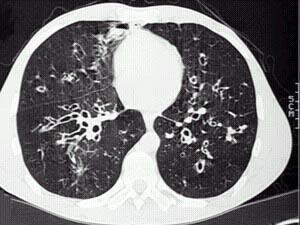

问题 女,36岁,咳嗽,咳痰,咯血,反复发作,CT检查如图,应诊断为 ( )

选项 A.双下肺支气管扩张并感染 B.多发性肺囊肿并感染 C.双下肺肺包虫病 D.间质性肺炎 E.肺气肿

答案 A